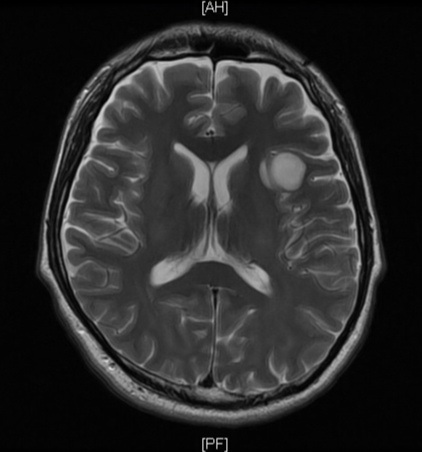

写真を載せておきます。脚から上に向かって画像を撮っています。

写真では右側に腫瘍が見えますが、自分から見れば左側です。

I have a photo that took the direction from legs to head.

The photo shows the tumor on the right side but left side on my sides